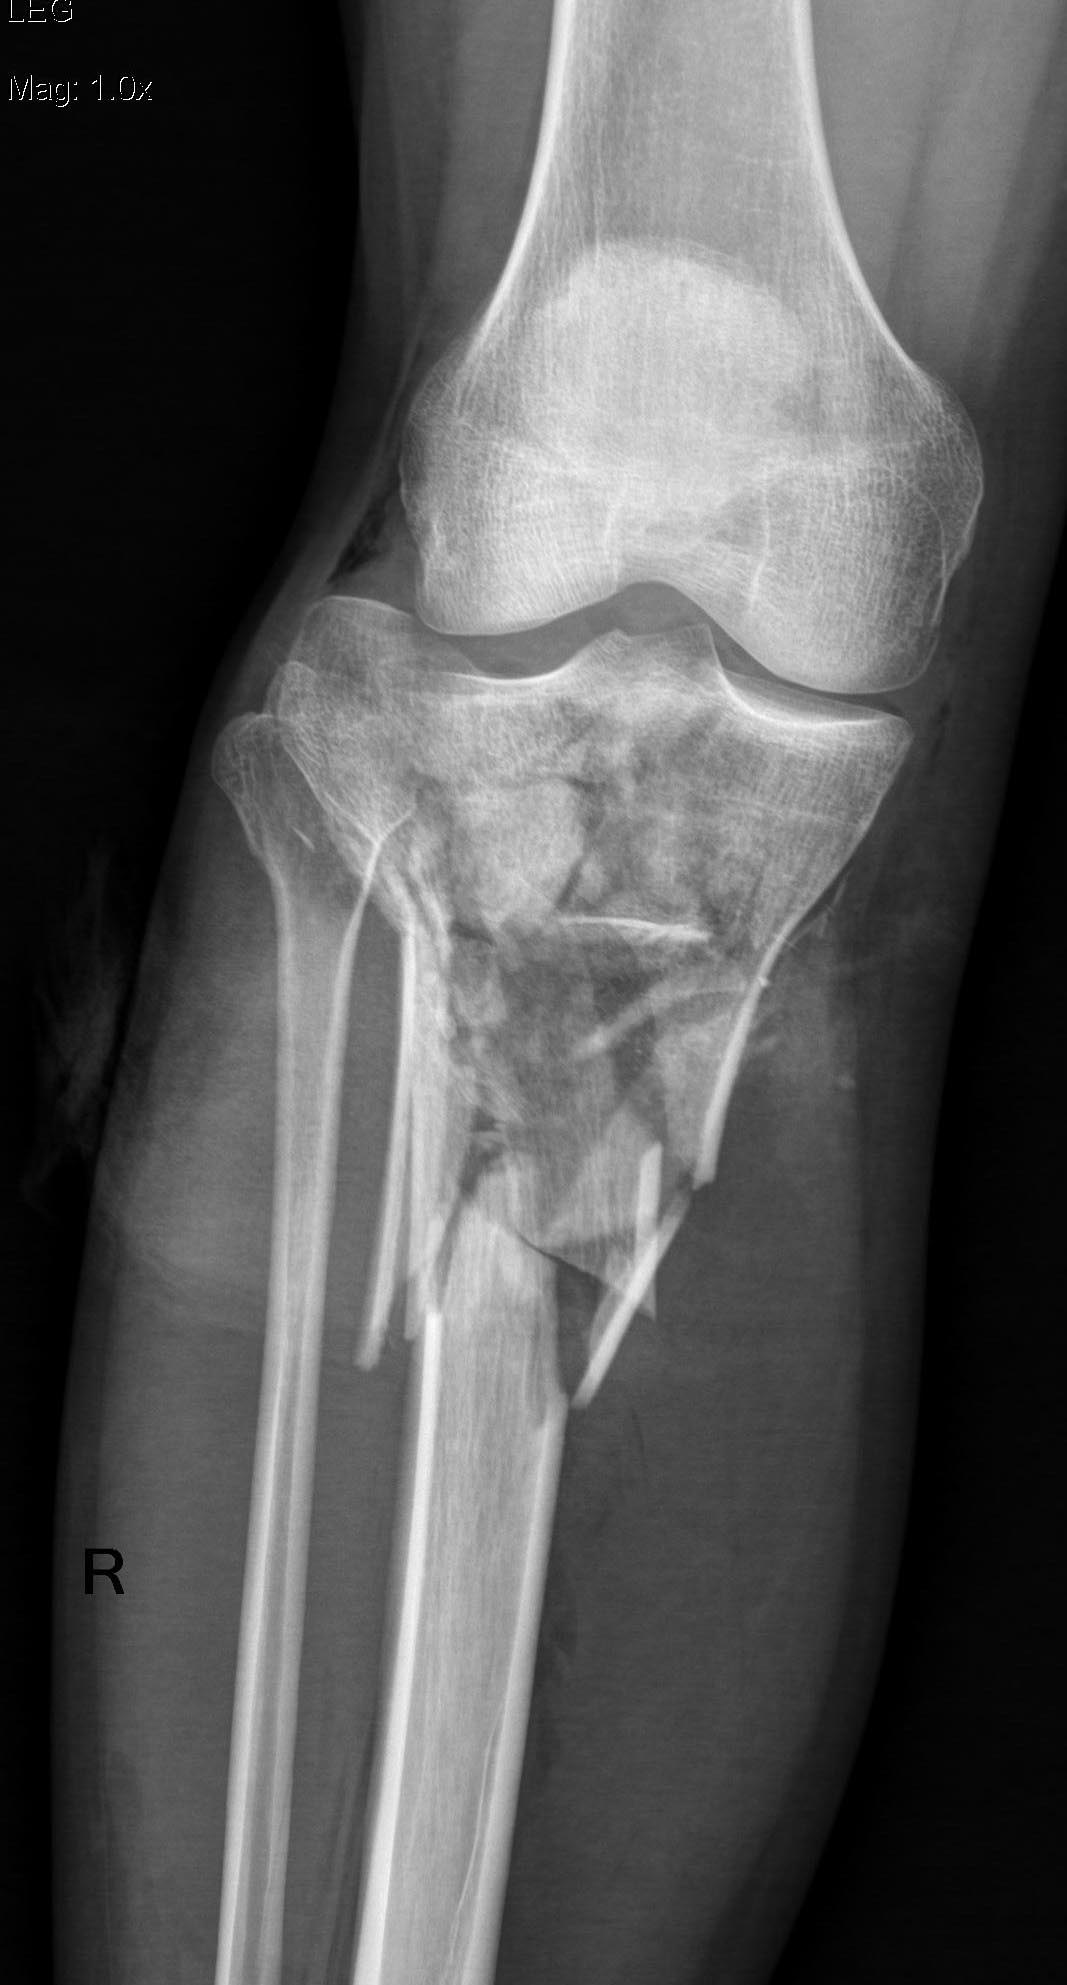

Уважаемые коллеги! Поступила пациентка после получения травмы в

результате столкновения с препятствием.

Имеется: Закрытый перелом диафиза левой локтевой кости. Закрытый

оскольчатый перелом диафиза левой бедренной кости в средней трети.

Открытые (3a-b) оскольчатые внутрисуставные переломы проксимального

отдела обеих костей правой и левой голени. (см. снимки)